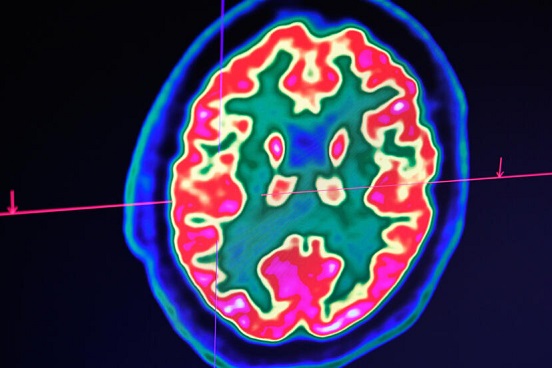

La curación, única en el mundo, de un niño con un glioma en el tronco cerebral, uno de los tipos de cáncer de cerebro pediátrico más mortales, da esperanzas a los científicos franceses. Pese a los avances en los tratamientos de los cánceres infantiles, este tumor, que afecta a entre 50 y 100 niños y adolescentes cada año en Francia, es un auténtico reto para los médicos.

Aunque la tasa de supervivencia a cinco años de un cáncer infantil es de 85%, algunos de ellos, como el glioma de tronco encefálico, tienen muy mal pronóstico. Este cáncer, inoperable, se trata normalmente con radioterapia, que permite a veces frenar el avance de la enfermedad, pero cuyo efecto es temporal. Todavía no hay ningún medicamento que sea totalmente eficaz.

La evolución es muy rápida y muchas veces el desenlace fatal llega entre 9 y 12 meses después de la detección del tumor. Un niño belga, Lucas, que tiene actualmente 13 años, rompió todos estos pronósticos: tras diagnosticársele a los 6 años esta enfermedad, prácticamente incurable, hoy se considera curado y su cerebro no presenta ningún signo del tumor.